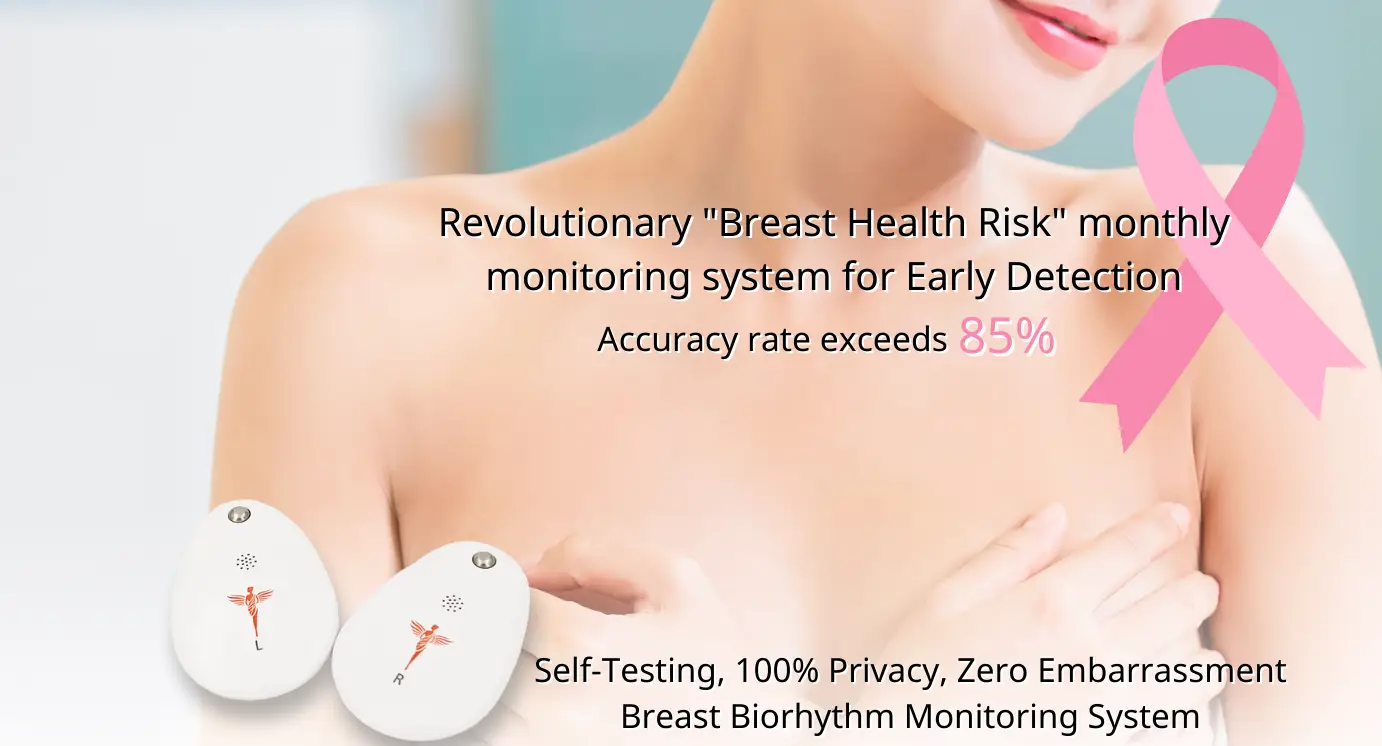

Breast Biorhythm Monitoring System

By utilizing the principle of cellular metabolic heat changes, cellular data is collected through smart sensors. The data is then uploaded to a cloud database for comparative analysis. After the analysis, the report is downloaded to the user’s mobile phone, providing health risk alerts and recommendations. Users can choose the next medical examination based on their needs, enabling home-based breast health risk management.